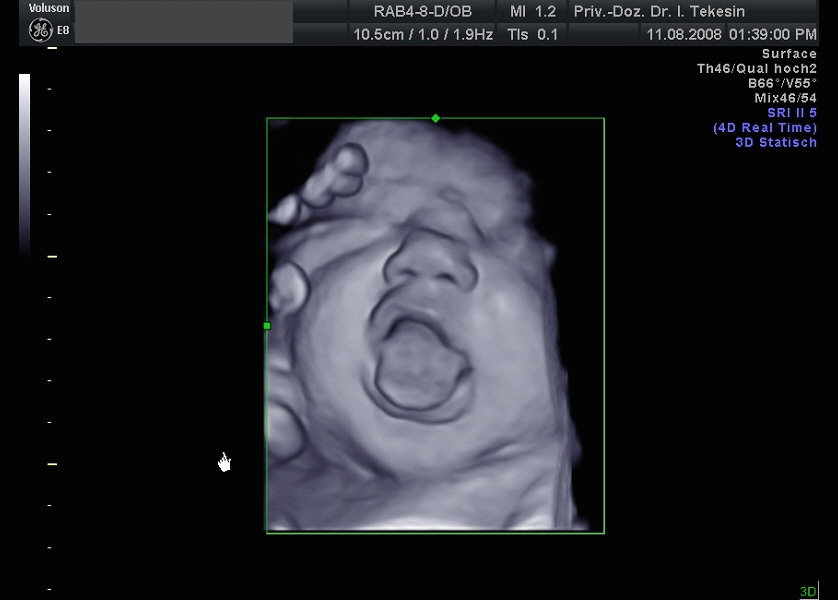

3D-/4D-Ultraschall (optional)

Immer mehr werdende Eltern interessieren sich für die faszinierenden Bilder, die dieses Verfahren liefert. Die plastische, dreidimensionale Darstellung der Oberfläche des Gesichts und anderer Körperregionen wird durch spezielle Bildrekonstruktion in schnellen Rechnern erreicht. Auch einzelne innere Organe oder „Gefäßbäume“ können von allen Seiten betrachtet werden. Viele dünne Schnittebenen (2D) werden zu einer gemeinsamen 3D-Sichtweise im Computer des Ultraschallgerätes zusammengeführt. Unter einem 4D-Ultraschall versteht man darüber hinaus eine 3D-Ultraschalluntersuchung unter Echtzeitbedingungen. Anstatt nur statische Bilder anzuzeigen, erfasst ein 4D-Ultraschall die Bewegungen des Kindes, weshalb er auch als „Live-3D-Ultraschall“ bezeichnet wird.

Diese Vorgehensweise ermöglicht äußerst realistische Bilder, bei denen sogar Gestik und Mimik des Kindes in bewegten Sequenzen festgehalten werden können. Die Untersuchung kann wie auch der normale Ultraschall während des gesamten Schwangerschaftszeitraums durchgeführt werden. Möchte man das Ungeborene komplett sehen, wird die 12. bis 16. Schwangerschaftswoche empfohlen, die Zeit zwischen der 28. und 33. Schwangerschaftswoche eignet sich besonders zur präzisen Darstellung einzelner Körperteile

Wir sehen in diesem modernen Verfahren in erster Linie eine ergänzende Maßnahme bei speziellen Fragestellungen bezüglich Herz, Gehirn oder Skelett und vor allem bei Verdacht auf eine fetale Besonderheit.

Ein gähnendes Kind in der 38. Woche

Ein freches Kind in der 38. Woche (3D-Darstellung)